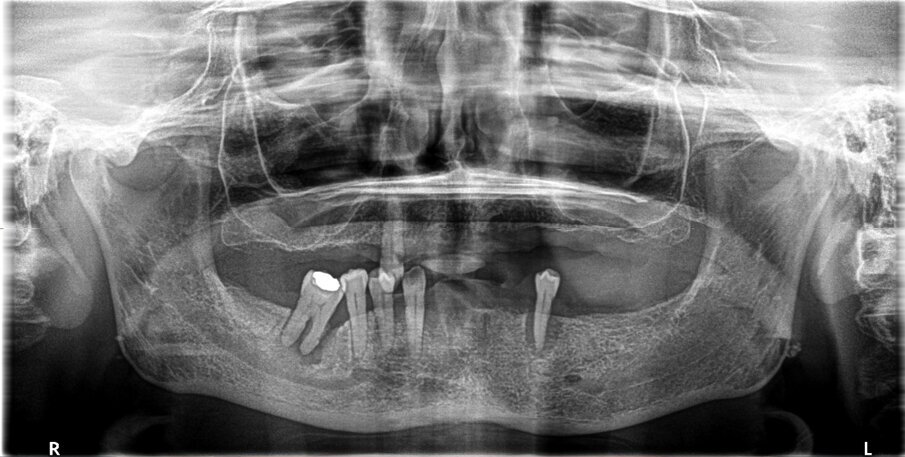

Fig. 10_Risultato finale.